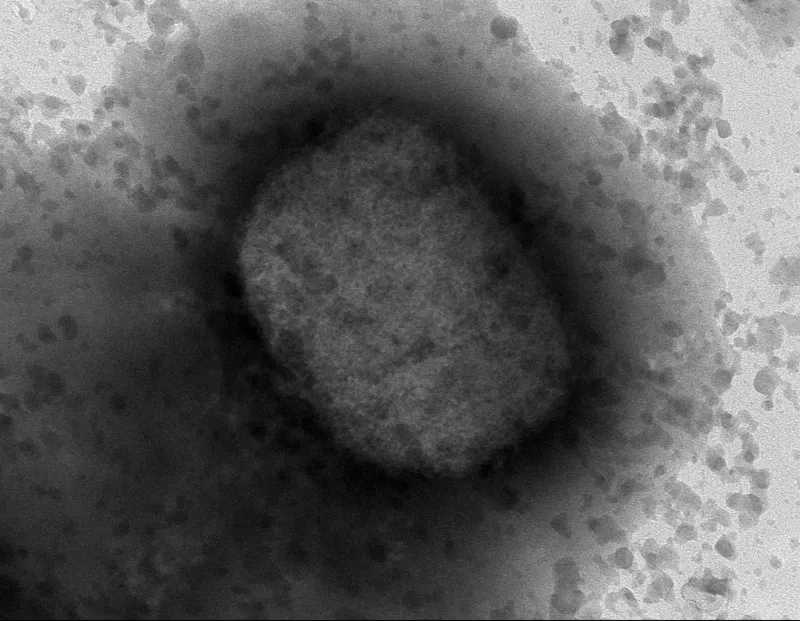

La secuencia completa del virus la obtuvo un equipo del Laboratorio de Arbovirus y de las Unidades de Genómica y Bioinformática en España. (Foto: EFE)

Investigadores del Instituto español de Salud Carlos III han conseguido el primer borrador de la secuencia completa del virus causante de la viruela del mono (Monkey Pox) que circula por España a partir de las muestras de 23 pacientes. En México ya se detectó el primer caso de viruela del mono .

La secuencia completa del virus la obtuvo un equipo del Laboratorio de Arbovirus y de las Unidades de Genómica y Bioinformática de este Instituto -dependiente del Ministerio de Ciencia e Innovación- y el logro permitirá hacer análisis más avanzados para obtener datos sobre su comportamiento y comprender mejor su origen, circulación y difusión.